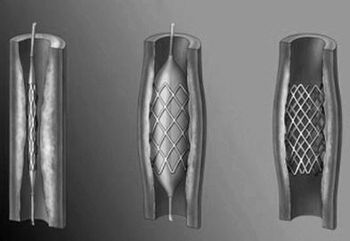

Пацієнтка Тетяна 47 років. Тривало страждала від мігрені (близько п'яти років), завжди лікувалася самостійно, за допомогою народної медицини, трав і різних примочок. Після того, як мігрень не відпускала протягом трьох днів, вирішила звернутися до лікаря. Після повноцінного обстеження, лікар встановив діагноз: Аневризми мозкових судин.

Медики відзначили можливі ризики розвитку інсульту у пацієнтки, було призначено стаціонарне лікування, а також рекомендовано подальше постійне спостереження за станом здоров'я, показниками АТ та ін.